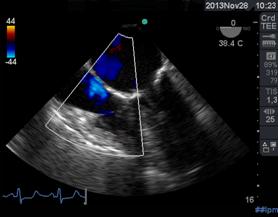

Por convención , el doppler espectral resultante muestra la velocidad en el eje de la Y y el tiempo en el eje X. El flujo que se dirige hacia el transductor, aparece por encima de la línea de base, mientras que el flujo que se aleja, se encuentra por debajo de la línea de base. El Doppler Color, (Figura 9) es una variedad de Pulsado que utiliza una escala de colores, representada, en el flujo laminar, con rojo (flujo que se acerca al transductor) y con azul el que se aleja. Cuando el flujo se hace turbulento, debido a una alteración funcional de la válvula, aparecen los colores amarillo y verde, reflejo de un aumento en la velocidad de la sangre al cruzar una válvula patológica anatómica o funcionalmente(13). (Figura 10)(Figura11)

Rojo positivo y laminar, se acerca a imagen transgástrica (140°), tracto salida transductor. Azul negativo, se aleja el transductor del ventrículo derecho (TSVD).

Figura 10 cuando la velocidad es elevada por flujo turbulento aparecen los colores amarillo y verde.

Figura 11: Izquierda: flujo turbulento por insuficiencia pulmonar leve. (TG profunda TSVD). Derecha: imagen a 66° medioesofágico 2 cámaras flujo turbulento por insuficiencia mitral moderada.